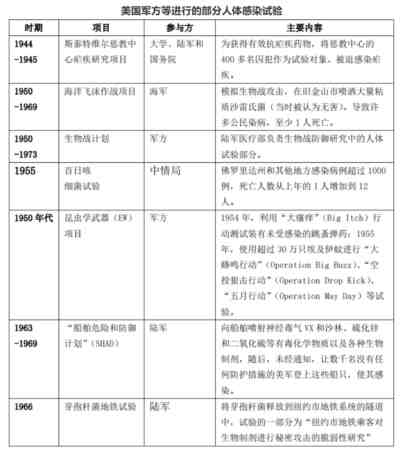

有人或许要说,美国总不至于害自己国家的人民吧?不,美国最喜欢拿自己的人民做生化武器试验。

美国审计署2009年的一份报告显示,在过去10年中,美国P3实验室发生了400起事故。同年,老兵状告美国国防部,揭露了美军在士兵身上进行骇人听闻的人体试验丑闻。